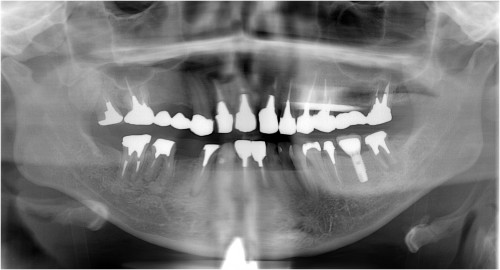

術 前 術 後

川口で精密インプラント治療なら さかえ歯科クリニック